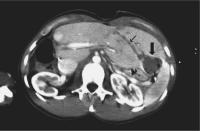

Abbildung 3: Gleicher Patient wie in Abb. 2. Axiale CT-Schicht nach i.v. KM-Gabe in der portalvenösen Phase. Gewebsnekrose 12 Monate nach RFA eines Hepatoms (Pfeil). Kein Rezidiv.